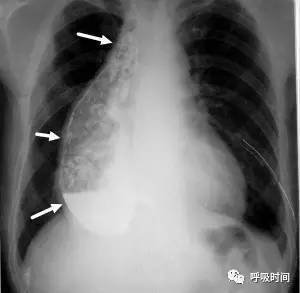

图片

图 12 粟粒影——急性血行播散性肺结核并右侧胸腔少量积液。双肺弥漫分布的粟粒影,呈典型的三均:大小均匀、分布均匀、密度均匀。右侧肋膈角变钝(蓝箭头)